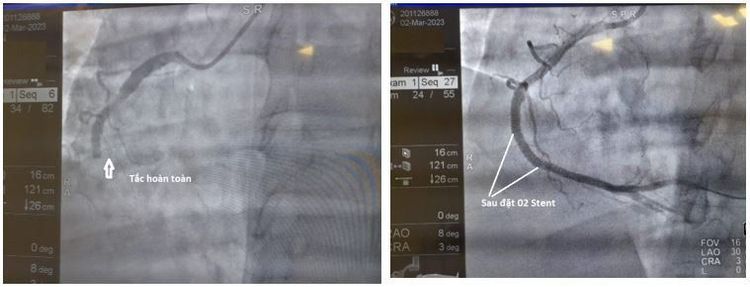

Một bệnh nhân 32 tuổi người Trung Quốc đã được đưa từ Móng Cái đến Bệnh viện ĐKQT Vinmec Hải Phòng do có cơn đau thắt ngực trái, khó thở. Với tiền sử hút thuốc lá nhiều năm, rối loạn Lipid máu không điều trị. Khi bệnh nhân nhập viện, với bệnh cảnh thăm khám, bác sĩ đã nghĩ đến tình trạng nhồi máu cơ tim động mạch vành. Tuy nhiên, trên siêu âm tim không thấy rõ rối loạn vận động vùng trên siêu âm tim, nghĩa là xét nghiệm không tương xứng với hình ảnh lâm sàng, bệnh nhân cần tầm soát bệnh lý động mạch chủ thêm để phân biệt với các bệnh lý động mạch chủ, bệnh lý động mạch vành. Kết quả là chụp MSCT động mạch chủ và động mạch vành cho thấy người bệnh có tình trạng tắc hoàn toàn động mạch vành phải từ đầu đoạn RCA3.

Với kết luận bệnh nhân bị hội chứng động mạch vành cấp, các bác sĩ đã có đủ cơ sở để đưa ra chỉ định can thiệp ngay và không cần trì hoãn nữa. Trong quá trình chụp động mạch vành qua da (DSA) để can thiệp đặt Stent cũng cho thấy kết quả tương xứng: Tắc hoàn toàn đoạn 3 của động mạch vành phải. Sau khi được can thiệp tái thông bằng 2 Stent, 3 ngày sau, bệnh nhân đã không còn các cơn đau ngực, vận động đi lại bình thường. Kết quả theo dõi nhiều tháng liền sau đó bệnh nhân dung nạp tốt, không có biểu hiện suy tim cho thấy các chẩn đoán và can thiệp là hoàn toàn chính xác và tối ưu.